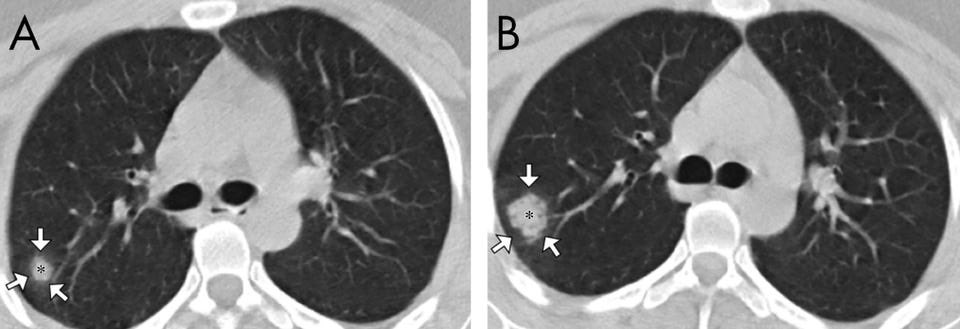

A Shanghai study also identified a mesh-like pattern called "reticulation," which is visible in this scan of a 75-year-old man.

According to the Shanghai researchers, 22% of the 50 patients they looked at displayed reticulation on their scans. Around 77% had ground-glass patches, while nearly 60% had consolidation — lung tissue that filled with liquid instead of air